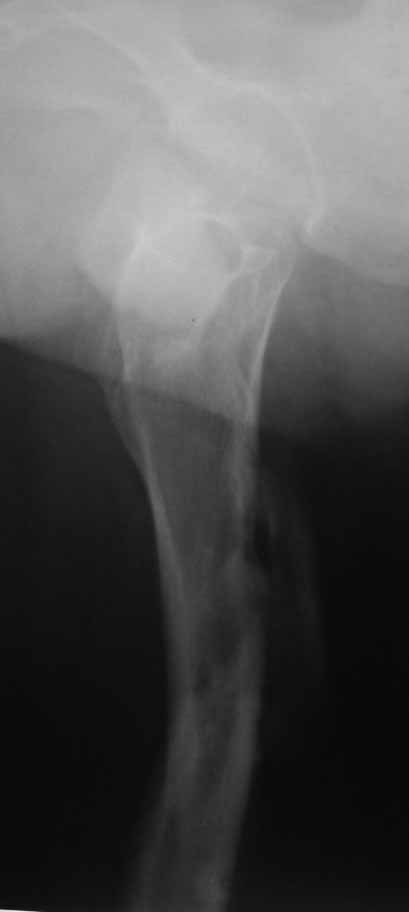

Уважаемые коллеги, доброго времени суток. Молодой парень 30 лет, в 2010г получил травму в результате ДТП. Лечили на скелетном вытяжени 6 нед с последующим наложением кокситной повязки на 12 нед. От предложенного остеосинтеза пластинами воздержался( БИОС к сожалению пока не доступен)В настоящее время ходит заметно прихрамывая, левая нижняя конечность укорочена сравнительно на 3,0 см. Объем движений в суставах полный. Как можно помочь больному в дальнейшем. Буду рад Вашим советам. Спасибо.

Здравствуйте Шухрат. Мне кажется, если хромата в результате укорочения конечности,а не из-за других причин, то оптимально будет произвести остеотомию в с/з и установить аппарат Илизарова.

Согласен с Вами, мое мнение нужно востоновить длину. В наших условиях это остеотомия и остеосинтез пластиной с учётом риска и осложнений, или же ему нужно будет оперироватся там где БИОС имеется.Был бы рад советам по поводу моего мнения.